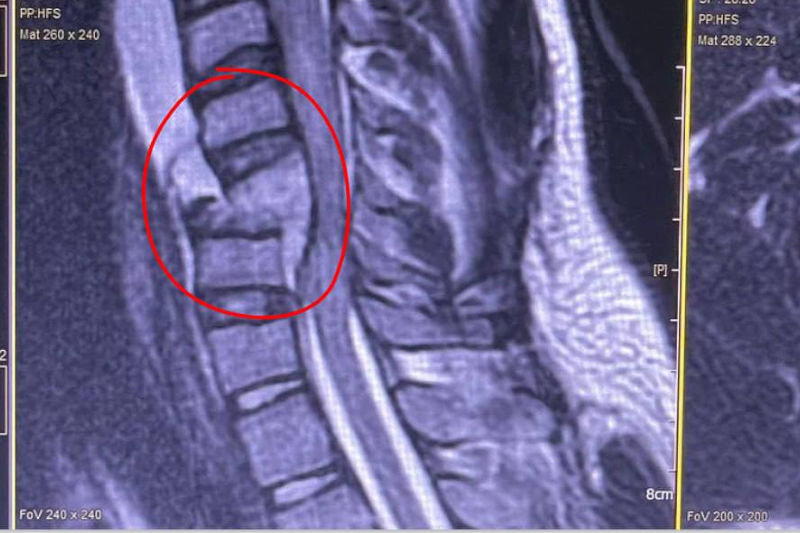

В комитете здравоохранения Волгоградской области рассказали: летом в региональный нейрохирургический центр ВОКБ №1 очень часто попадают молодые пациенты с переломами шейного отдела позвоночника. В начале этой недели врачи-нейрохирурги ВОКБ №1 прооперировали молодого пациента. Не узнав уровня воды, он нырнул вниз головой в мелководье и в нескольких местах сломал позвоночник. Нейрохирурги диагностировали: полностью разрушены передние отделы 5-го шейного позвонка, нарушена статика шейного отдела позвоночника, в зоне перелома — гематома, мягкие ткани сильно повреждены.